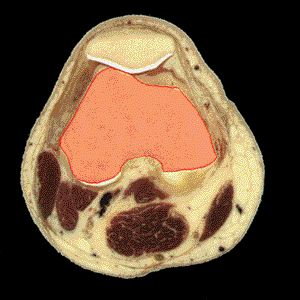

FEMURDefinición: El fémur, el hueso del muslo se articula en la cadera y la rodilla. Es el hueso más largo y robusto del cuerpo. Origen: La caña del fémur se curva anteriormente a lo largo de su eje longitudinal y se ensancha ligeramente en sus extremos. La superficie del fémur es lisa con la excepción de un grueso cordón posterior - la línea aspera - que es utilizada como punto de inserción de los músculos biceps femoral, abductor mediano, abductor menor, y porciones del abductor mayor. Inserción:

El fémur distal muestra los cóndilos lateral y medial

para su articulación con la tibia. El cóndilo medial se

extiende más distalmente que el cóndilo lateral. Los cóndilos

están separados por una depresión llama "fosa intercondílea".

Próximos a los cóndilos se sitúan las tuberosidades

interna y externa del fémur donde se insertan los ligamentos

lateral interno y lateral externo, respectivamente. En la fosa intercondílea

se insertan los ligamentos cruzado anterior y cruzado posterior. |